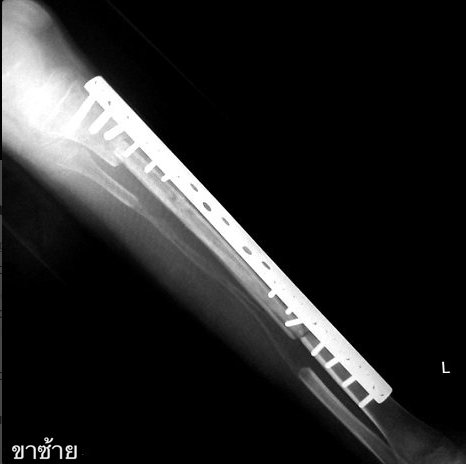

RÖNTGENDE ORTAYA ÇIKTI

Muay Thai dövüşçüsü Bandasak Chaiyasan, çelikten kaval kemiği olduğu gerekçesiyle müsabakalardan birine ciddi zarar veremeden men edildi. Dünya Muay Thai Konseyi, Noppadon Chalor - Bandasak Chaiyasan müsabakasında gerçekleşen nakavt sonucu Chaiyasan'ın kaval kemiğinin röntgenini çekme talebinde bulundu. Röntgende kaval kemiği titanyumdan yapılma bir plakayla kaplanan Chaiyasan, konsey tarafından ringlerden uzaklaştırıldı.